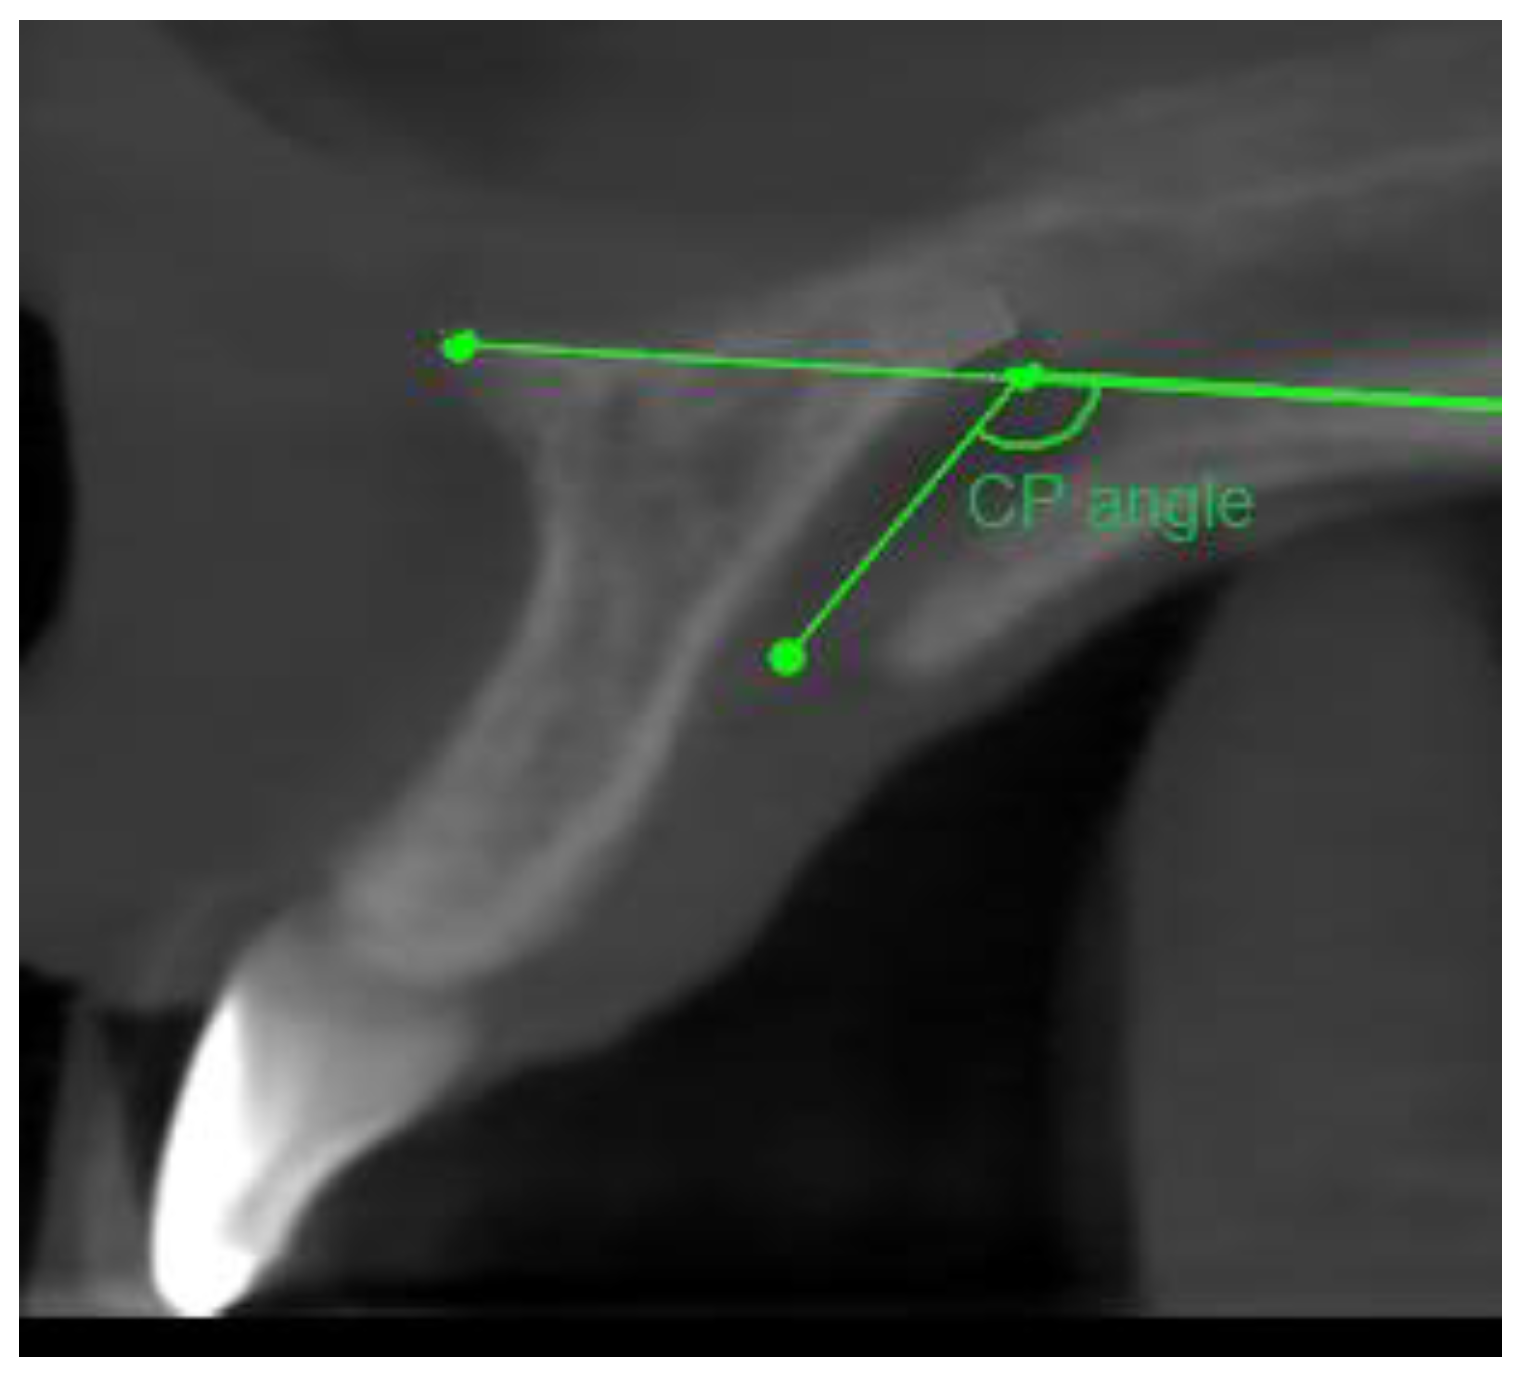

- Angle formed by the long axis of the incisor and the palatine plane—CP angle.